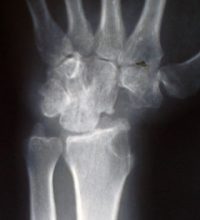

Η διάγνωση επιβεβαιώνεται με ακτινολογικό έλεγχο, αξονική και μαγνητική τομογραφία.

Αρθρόδεση 4 οσταρίων, «4 Bone Fusion», ή « 4 Corner Fusion», είναι από τις πλέον χρησιμοποιούμενες και αποτελεσματικές στη θεραπεία της καθίζησης του καρπού.